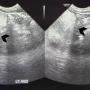

Abdominal ultrasound showed a large lobulated hyperechoic mass occupying abdomen and pelvis (black arrowhead)